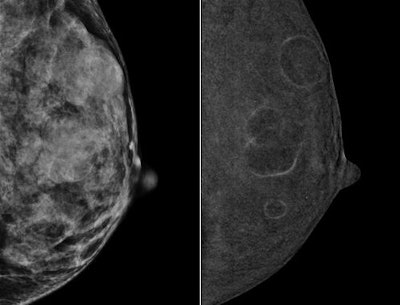

Left mediolateral oblique (MLO) digital mammography image (left) from a 49-year-old high-risk patient with extremely dense breasts. CEDM image (right) shows multiple benign rim-enhancing masses compatible with benign cysts. Images courtesy of Dr. Bhavika Patel.Real relief